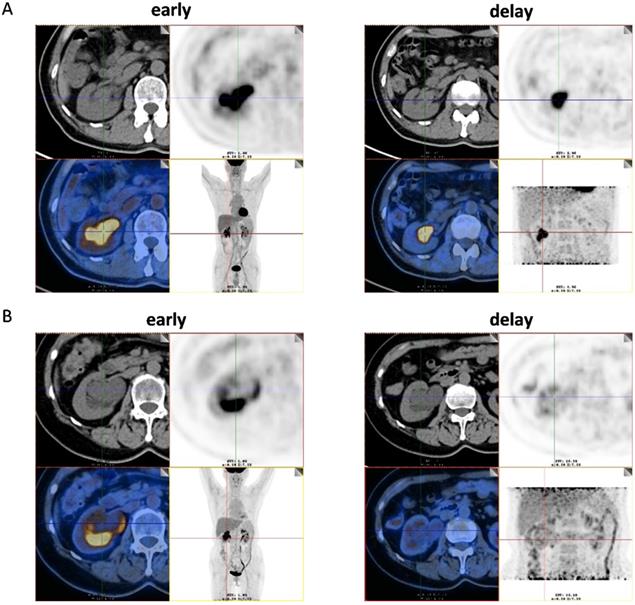

Among the 51 patients, 47 had malignant tumors: these included 40 cases of high- grade urothelial carcinoma, 4 cases of low-grade urothelial carcinoma and 3 cases of unclassified urothelial carcinoma. The remaining 4 patients had benign lesions, which were confirmed as benign polyp. Patient characteristics were shown in Table 1. The scatter plot of maximum standardized uptake value (SUVmax) for each urothelial carcinoma grade and benign polyp is shown in Figure 1. Mean SUVmax for high-grade urothelial carcinoma, low-grade urothelial carcinoma and benign polyp were 17.9 ± 9.7, 15.3 ± 8.6 and 3.8 ± 1.6, respectively. Both high-grade urothelial carcinoma (17.9 ± 9.7 vs 3.8 ± 1.6, P < 0.001) and low-grade urothelial carcinoma (15.3 ± 8.6 vs 3.8 ± 1.6, P = 0.039) showed significantly higher SUVmax compared with the benign polyp. However, there was no significant difference in SUVmax between high-grade urothelial carcinoma and low-grade urothelial carcinoma (17.9±9.7 vs 15.3 ± 8.6, P = 0.651). Representative images of a patient with renal pelvic carcinoma with high SUVmax (SUVmax=14.1) (Fig. 2A) and a patient with benign polyp with low SUVmax (SUVmax=2.9) (Fig.2B) who underwent early PET/CT imaging and delayed post-diuretic PET/CT scanning were shown in Figure 2.

(A) Images of a 56-year-old man with renal pelvic cancer with high SUVmax (SUVmax=14.1). On the 18F-FDG PET/CT images, axial CT show that the space-occupying lesion was located in right renal pelvis. However, the 18F-FDG uptake of lesion cannot be easily detected because of urine interference in the early image (early). On the image of 18F-FDG PET/CT in the delayed phase, the ureter is distended and lesion can be easily visualized by axial CT and PET (SUVmax, 14.1) (delay) as the 18F-FDG uptake of urine was very low. The patient underwent radical resection of renal pelvic cancer, and low-grade urothelial carcinoma was confirmed by histopathology. (B) Images of a 61-year-old woman with benign polyp with low SUVmax (SUVmax=2.9). On the 18F-FDG PET/CT images, axial CT show that the space-occupying lesion was located in right renal pelvis. However, the 18F-FDG uptake of lesion cannot be easily detected because of urine interference in the early image (early). On the image of 18F-FDG PET/CT in the delayed phase, the ureter is distended and lesion can be easily visualized by axial CT and PET (SUVmax, 2.9) (delay) as the 18F-FDG uptake of urine was very low. The patient underwent pyeloureterectomy, and benign polyp was confirmed by histopathology.